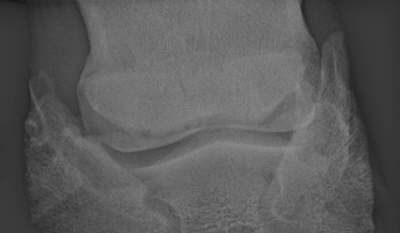

Deutliche Zubildung am unteren rechen Strahlbeinrand. Sonst relativ unauffällig.